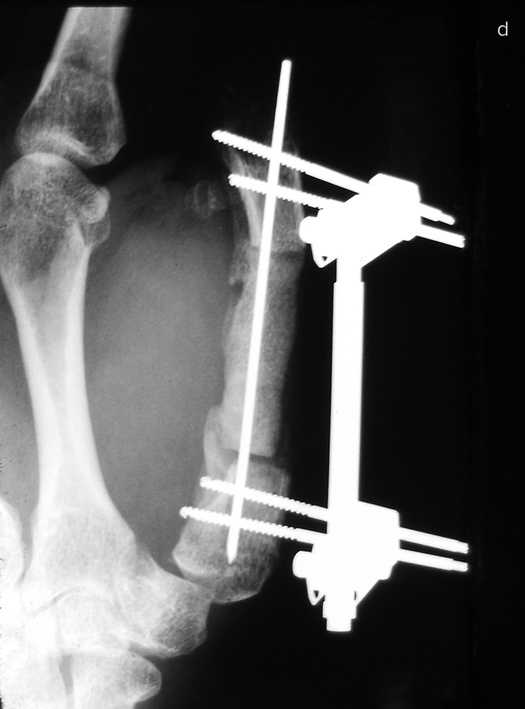

Если восстановить или приживить эту важнейшую часть кисти невозможно, ее реконструируют. Существует три основные методики, которые я условно называю «упросить», «одолжить» и «украсть». В первом случае хирург и пациент как бы упрашивают обрубок большого пальца вырасти в длину. С обоих концов оставшейся кости хирург вставляет поперечные стальные шпильки, прикрепляет эти шпильки к стальной раме и разрезает кость между ними.

Пациент каждый час поворачивает небольшую ручку этого приспособления, напоминающего аппарат Илизарова, и по чуть-чуть увеличивает промежуток между фрагментами кости. Процедура длится от шести до восьми недель. Кость и окружающие ее мышцы, сухожилия, нервы и кожа едва ли понимают, что их растягивают: для них это просто какой-то очень быстрый рост, и им надо успеть.

Когда большой палец вновь обретает рабочую длину, хирург заполняет промежуток костным трансплантатом. Преимущество такого способа удлинения в том, что не приходится ничего «одалживать» или «красть». Однако не все так радужно: ноготь и отсутствующие суставы большого пальца уже не вернуть.